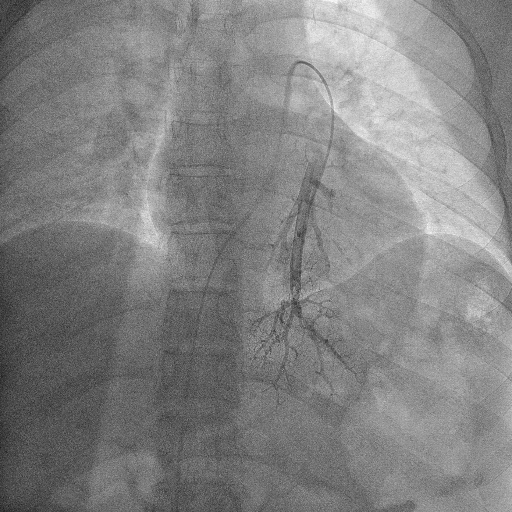

A twenty nine years old lady diagnosed as Carcinoma left breast underwent breast conservation surgery (pT2N2aM0, ER positive PR positive Her 2 neu positive) and presented for adjuvant chemotherapy. She was planned for adjuvant chemotherapy, radiotherapy and hormonal therapy as per standard guidelines. Chemoport reservoir was placed in the chest wall – right infraclavicular fossa and chemoport catheter was placed in the right subclavian vein. Post-procedure chest x ray revealed proper placement of the chemoport. She underwent first cycle of adjuvant chemotherapy with Docetaxel, Carboplatin and Trastuzumab without any complications. When she presented for second cycle (45 days after chemoport insertion), she was asymptomatic. However, there was no backflow of blood from the chemoport reservoir. Chest X ray revealed fragmentation and embolization of chemoport catheter. ECG showed normal sinus rhythm. Non Contrast CT scan chest was done, which revealed that the distal fragment of chemoport catheter had embolized to left pulmonary artery lower lobar branch, having migrated across the right atrium, right ventricle, main pulmonary artery and its left branch (Figure 1). After informed consent, retrieval of distal fragment of chemoport catheter was done in cath lab under local anesthesia under fluoroscopic guidance by Interventional Radiology team. It was retrieved from left pulmonary artery lower lobar branch in a procedure lasting forty minutes. The right femoral vein was punctured, 10 Fr Cordis sheath was introduced into the femoral vein, left pulmonary artery was cannulated using cobra 5 Fr catheter and then it was exchanged with snare over the guide wire. The left posterior inferior branch of pulmonary artery was selectively cannulated using Terumo guide wire and Cobra catheter. The tip of the foreign body was snared using Sequre snare system (4Fr, 10mm) and pulled through the pulmonary artery (Figure 2). The length of the catheter fragment was 4cm (Figure 3-9). The next day, chemoport reservoir and the proximal fragment of chemoport catheter was retrieved by surgery under local anesthesia. Patient tolerated both procedures well and was discharged on the third day.

Figure 6 Fluoroscopy image of Catheter pulmonary angiogram showing the foreign body in left pulmonary artery branch.

Figure 7 Fluoroscopy image of Catheter pulmonary angiogram showing foreign body as a filling defect in the lower lobar branch of left pulmonary artery.